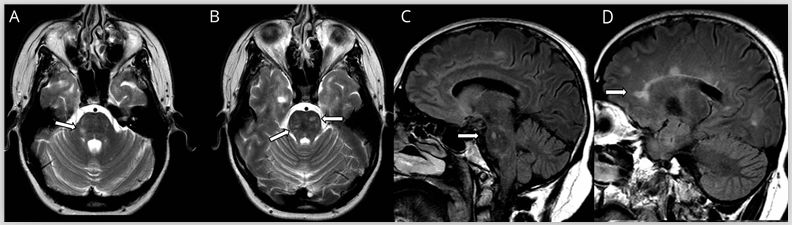

多发性硬化(MS)是中枢神经系统的获得性炎性脱髓鞘疾病,在MRI上病灶通常为卵圆形且界限清晰,T2和FLAIR序列呈高信号改变(图1)。在慢性病变过程中当轴突受损时,T1序列上可见低信号的黑洞征,但急性期也可能见到。新发病灶在3天到3个月内(平均3周)可见强化。虽然MS病灶会出现弥散受限,但当弥散发生变化时,弥散率通常会增加。当存在弥散受限时,特别是多发病灶和不在典型部位时,应考虑其他病因,例如SS或血管炎。

MS的病灶通常发生在脑室周围、胼胝体周围、深部白质、皮层和近皮层部位、脑干、小脑以及视神经和脊髓。在T2 *序列上的中心静脉征有助于MS病变与其他炎性和非炎性疾病(包括NMOSD)的鉴别,超过80%的MS病变位于静脉周围。而相比之下,NMOSD为32%,CNS血管病变为14%。

MS常累及脑干,在儿科MS中可能更常见。脑干病变可预测临床孤立综合征的残疾程度及向MS转化的概率。核间性眼肌麻痹(INO),尤其是年轻患者双侧INO高度提示MS。

MS病灶通常位于脑干的外围,如脑桥前部或三叉神经进入区,或位于导水管周围灰质的腹侧,而慢性小血管疾病会影响穿支动脉的区域(例如脑桥中央),并常伴有其他血管病变(腔隙性梗塞或微出血)。

与NMOSD不同,MS更容易发生于脑桥,并且在背侧和腹侧脑干中均可发生。脑干中孤立的MS样脱髓鞘病变可能是所谓的孤立性硬化症的唯一表现,少数(7%)患者表现为短暂的增强。

图1多发性硬化症患者的MRI影像。轴位T2加权(A,B)显示脑桥外围界限清楚的卵圆形病灶(箭头)。矢状位FLAIR图像(C,D)显示胼胝体下表面的病灶(C)和垂直于胼胝体的病灶(Dawson指征)(D)。